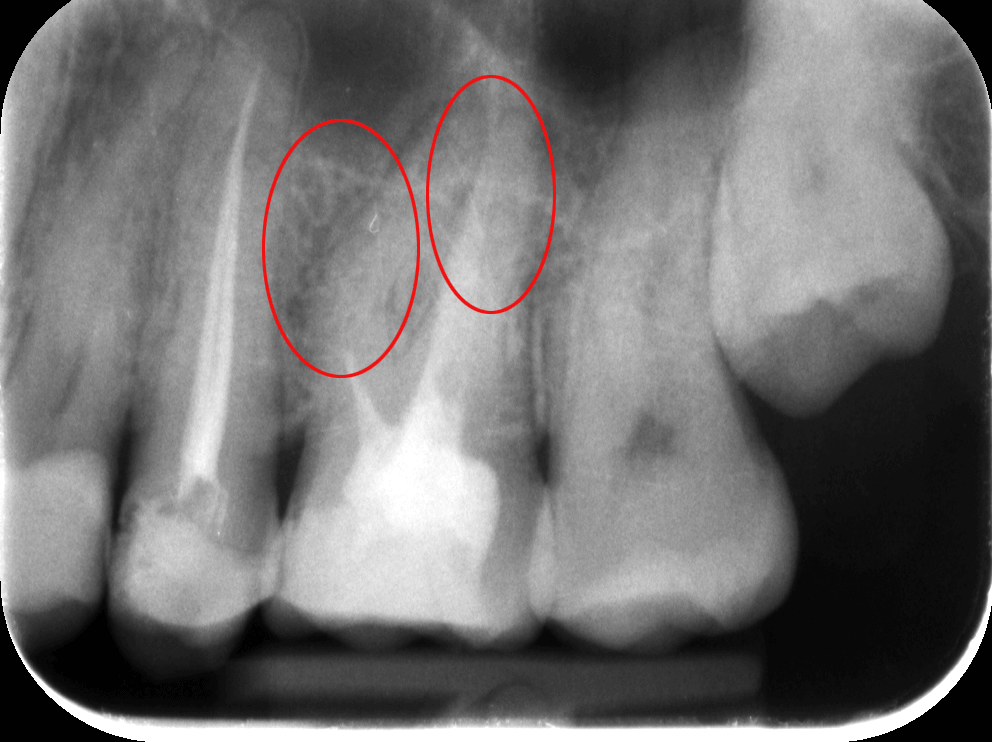

Az elkészült röntgenfelvételeken tehát a sötétebb területek jelzik a gyulladás fennállását (pirossal bekarikáztuk), a foggyökércsatornák halványabban látszanak, elmosódottabbak vagy teljesen eltűnnek a felvételen.

Dr. Molnár Katalin mikroszkópos berendezéssel szakszerűen elvégezte a fogtömés cseréjét. Ezen a képen ugyanaz a fog látható már a gyökértöméscsere után. Megfigyelhető, hogy a sötét területek kivilágosodtak. Ez arra utal, hogy a gyulladás gyakorlatilag megszűnt, a fog gyógyultnak tekinthető.